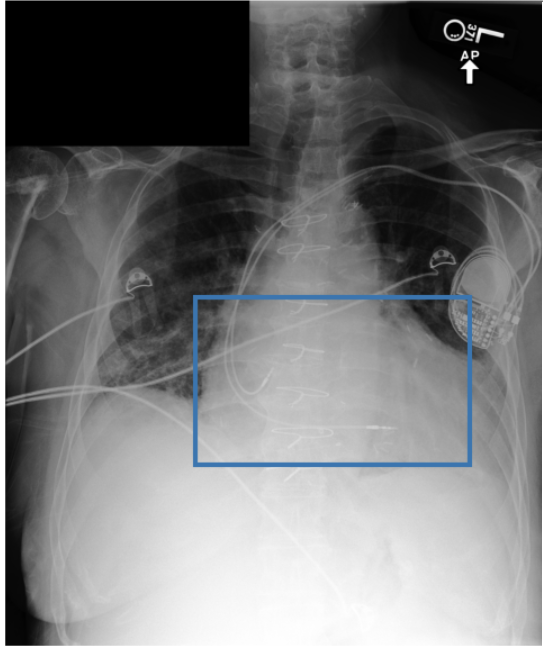

To address these drawbacks, state-of-the-art models such as MAIRA-2 [3] explicitly incorporate grounded report generation to better align local visual evidence with the textual findings. For example, MAIRA-2 is trained on a diverse set of localization-based tasks, including phrase grounding and grounded report generation. However, as shown in Figure 1, current models often exhibit a bias in which the target visual regions become overly associated with abnormal findings, leading to false positives in medical reports.

As shown in Table 1, our data composition reflects this imbalance: over 12.9M instances from Chest ImaGenome dominate the much smaller MS-CXR (815 PG instances) and PadChest-GR (12k instances) datasets. Beyond the imbalance between datasets, each dataset also exhibits substantial intra-dataset class imbalance. For example, anatomical regions in AGRG and semantic categories in PG are unevenly represented, leading the model to overfit frequent regions, neglect rare but clinically important ones, and hallucinate findings (Figure 1). Our curriculum framework addresses both sources of imbalance.

While MAIRA-2 exhibits a slightly lower hallucination rate for a few anatomies (e.g., ‘Cardiac Silhouette’), CURE consistently achieves a significantly lower contradiction rate and higher entailment rate across almost all categories. This improved performance likely stems from a key difference in the training data composition. Standard phrase grounding, used by MAIRA-2, is inherently biased towards abnormal findings. In contrast, our AGRG formulation exposes the model to both normal and abnormal descriptions for each anatomical region, leading to a more balanced and reliable generative process that mitigates the tendency to hallucinate abnormalities.